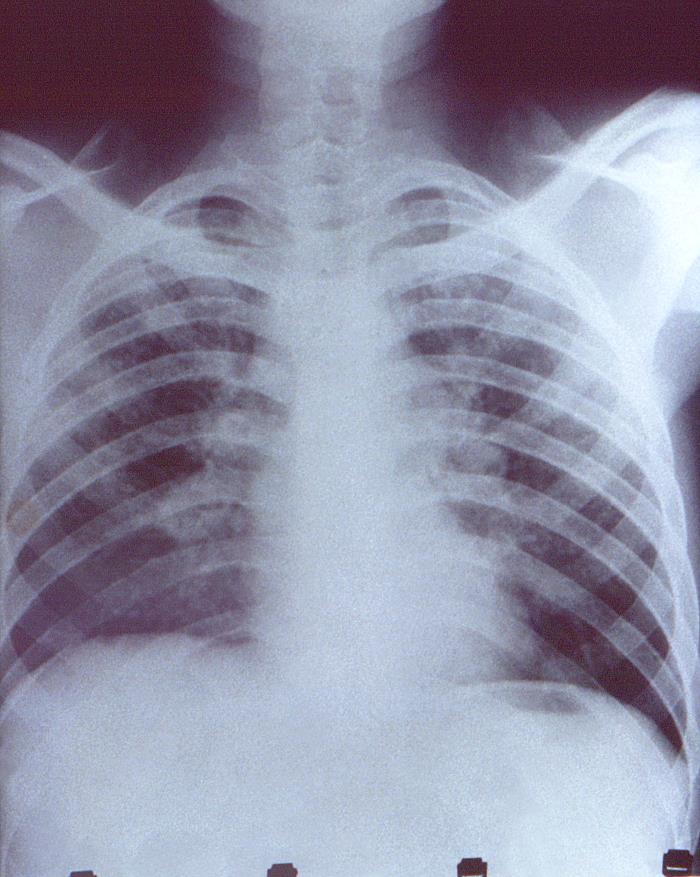

This anteroposterior (AP) chest x-ray revealed the presence of bilateral adenopathy, and bilateral infiltration in a patient with a case of cryptococcosis, due to the fungal organism of the genus, Cryptococcus.